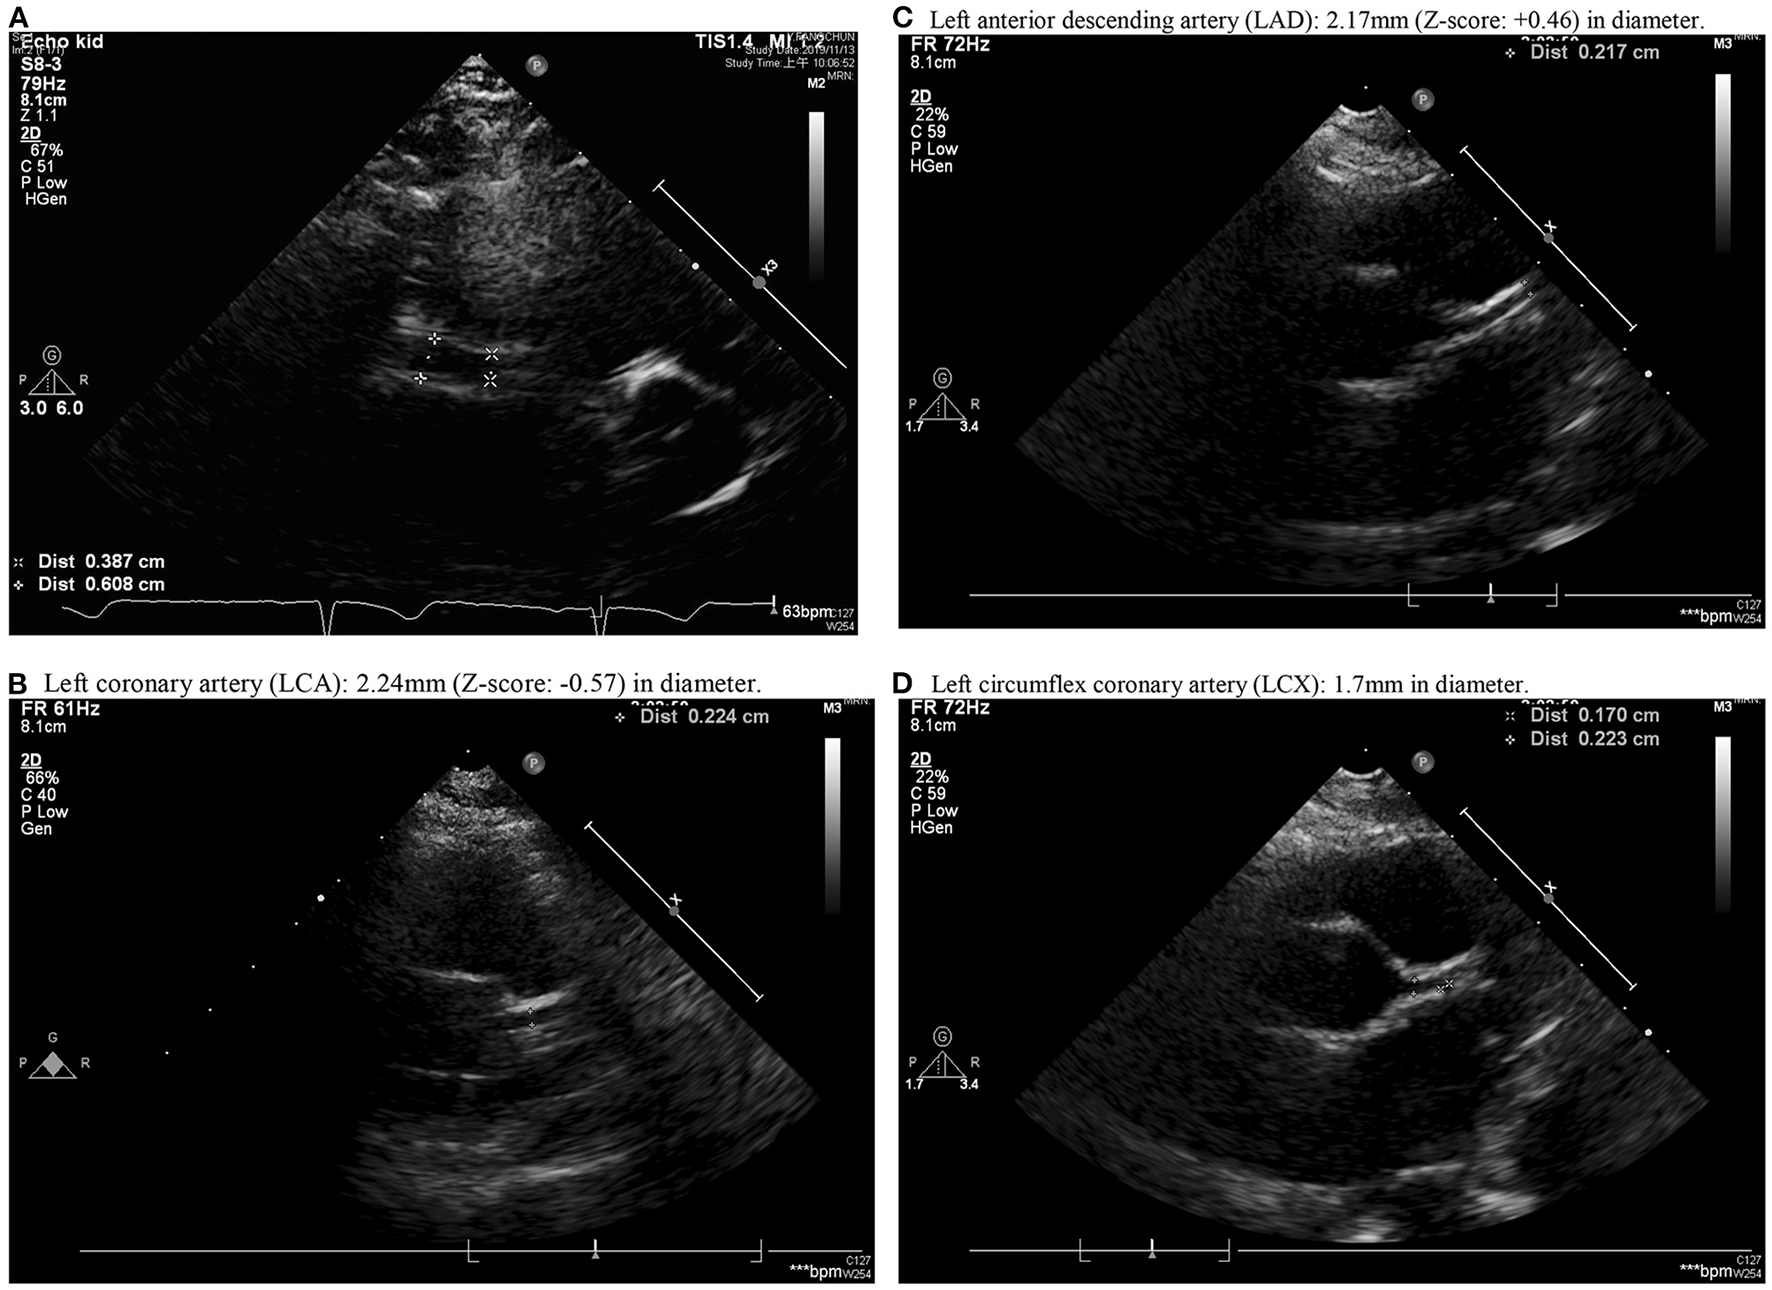

A previously healthy 10-year-old Taiwanese boy presenting with a high fever for 12 days was admitted to another hospital in year 2019. Prior to admission to our hospital, he showed bilateral conjunctival injection, erythema of the lips and neck, and lymphadenopathy. No BCG site induration was observed, nor was skin rash or limbs induration found. After the patient was admitted to our pediatric ward, the laboratory analysis revealed evidence of mild leukocytosis (10,600/μl), thrombocytosis (557,000/μl), and high C-reactive protein (CRP) (132.22 mg/L), without acute liver or kidney injury. A two-dimensional echocardiography on day 1 of admission (day 12 of illness) revealed a 4.12 mm aneurysm (BSA-adjusted Z score = 3.17) of the right coronary artery (RCA) with general dilatation of the RCA and LCA. High-dose intravenous immunoglobulin (IVIG, 2 g/kg) infusion was prescribed during admission (day 12 of illness). After being discharged, the RCA still progressed to a mid-sized aneurysm 6.08 mm (Z score: 4.85) in diameter and 35 mm in length (day 20 of illness) (Figure 1). Parents were directed to give hydrogen gas inhalation at least 1 h per day for the patient (77% hydrogen with 23% oxygen, 70~75 liter/hour) at home by themselves until aneurysm regression. The follow-up echocardiography showed regression in the aneurysm, which was then 5.37 mm in diameter and 12 mm in length of RCA (day 34 of illness) and 4.56 mm × 8.68 mm (day 48 of illness), then 4.16 mm (day 62 of illness). The mid-sized aneurysm regressed to within normal range with 2.91 mm in diameter (Z score = 1.46) on day 138 of illness (Figure 2). The following laboratory data showed normal liver enzyme (aspartate aminotransferase/ alanine aminotransferase: 24/17 U/L), renal function (blood urine nitrogen/creatinine: 18.0/0.52 mg/dl, estimated glomerular filtration rate: >60 ml/min), total white blood cell count: 11,800/ul (leukocytosis), hemoglobin: 14.2 g/dl, platelet: 258,000/ul, segment: 67%, lymphocyte: 26%, monocyte: 5%, eosinophil: 0%, basophil: 0%, sodium: 143 mEq/L, potassium: 3.7 mEq/L, chloride: 107mEq/L, albumin: 4.6 g/dl, calcium: 9.7 mg/dl, eosinophil cationic protein: <2.0 microgram/L and total immunoglobulin E: 107 KU/L. The laboratory data from acute and chronic stage (after hydrogen gas inhalation) were showed in Table 1. We reported on this case using a medical chart review retrospective, and the institutional review board (IRB) of Chang Gung Memorial Hospital approved this study (IRB No.: 201900827B0).

Figure 1

Aneurysm formation over middle right coronary artery (RCA) with a diameter of 2.9 mm near the ostia, gradual dilation to maximum diameter of 6.08 mm near the middle 1/3 of RCA with length of 3.5 cm and distal RCA diameter of 3.11 mm (posterior AV groove) (A). (B–D) showed Left coronary artery (LCA), Left anterior descending artery (LAD) and Left circumflex coronary artery (LCX). (B) Left coronary artery (LCA): 2.24 mm (Z-score: −0.57) in diameter. (C) Left anterior descending artery (LAD): 2.17 mm (Z-score: +0.46) in diameter. (D) Left circumflex coronary artery (LCX): 1.7 mm in diameter.